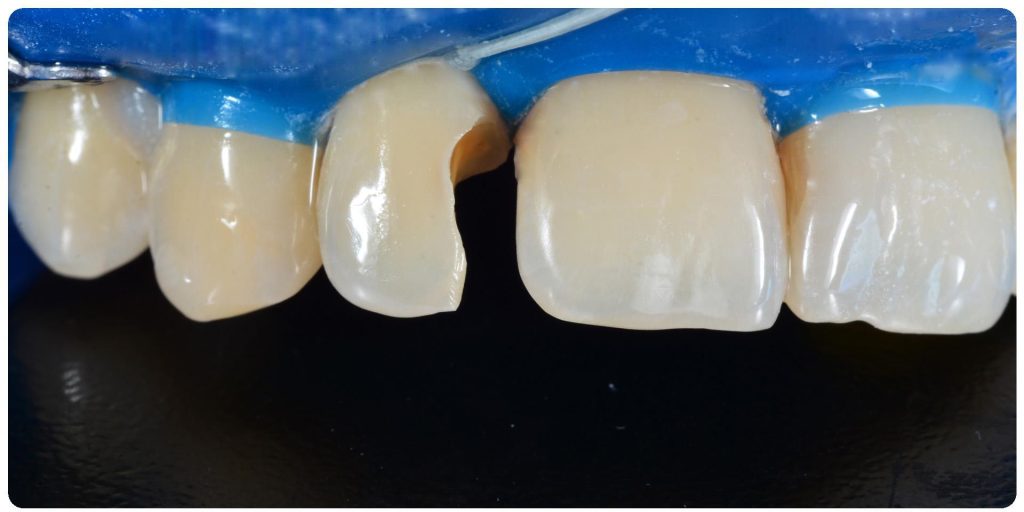

Aby osiągnąć taki efekt, musieliśmy przeprowadzić ekstrakcję złamanej górnej jedynki i w jej miejsce jednoczasowo wszczepić implant, a następnie na pozostałe zęby wykonać licówki i korony pełnoceramiczne w najjaśniejszym odcieniu.

Całość została zaprojektowana w harmonii z twarzą i rodzajem uśmiechu naszej Pacjentki. Leczenie trwało 3 miesiące.

Wykonał je lek.stom. Michał Badowski we współpracy z laboratorium Dentalscan (tech.dent. Joanna Gancarz).